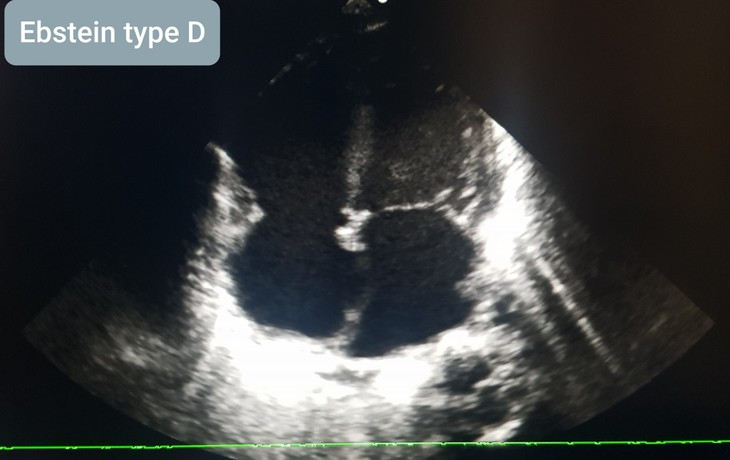

Ngay khi tiếp nhận bệnh nhân, nhận định tình trạng trẻ rất nặng, các bác sĩ đã ngay lập tức hồi sức, cấp cứu cho bệnh nhân. Trẻ được chẩn đoán Ebstein type D/ Suy tim độ III/ Nhịp nhanh nhĩ và được cấp cứu sốc điện tim, thở máy, dùng duy trì thuốc trợ tim và nuôi dưỡng hoàn toàn tĩnh mạch. Sau 13 ngày điều trị tích cực, tình trạng bệnh nhi đã cải thiện.

Theo đánh giá của bác sỹ Khoa Tim mạch – Lồng ngực, Bệnh viện Trẻ em Hải Phòng, bất thường Ebstein là một bệnh lý tim bẩm sinh nặng với tần suất 1-5/20.000 trẻ sơ sinh sống, tỉ lệ khoảng 1% trong nhóm tim bẩm sinh. Đặc trưng bởi sự di chuyển về phía đỉnh tim của lá vách và lá sau của van 3 lá.

Điểm tiếp xúc của các lá van được hạ xuống tâm thất phải. Kết quả là nhĩ phải mở rộng và tâm thất phải nhỏ (tâm nhĩ hóa Thất phải) và làm tắc nghẽn đường ra thất phải của tim.

Bất thường ebstein cũng thường đi kèm những bất thường tim mạch khác như Thông liên nhĩ, hẹp động mạch phổi, thông liên thất hay bất thường về nhịp tim làm tăng tiên lượng nặng cho bệnh nhân.

Bất thường Ebstein cũng như các dị tật tim bẩm sinh nói chung là bệnh có thể chẩn đoán sớm và chính xác bằng Siêu âm tim. Đây là một kỹ thuật không xâm lấn, không xảy ra tác dụng phụ. Bệnh tim bẩm sinh nếu được phát hiện sớm và có biện pháp can thiệp đúng, kịp thời có thể giúp trẻ tăng trưởng, phát triển và có cuộc sống gần hoặc như những trẻ bình thường.